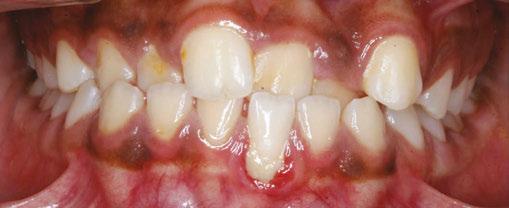

Figure 1: Initial center photo

This case involves a 13-year-old female patient with a complex malocclusion that includes multiple dental and skeletal issues. During the initial consultation, clinical evaluation showed severe maxillary crowding along with generalized spacing in the mandibular arch. The patient’s occlusal relationships were asymmetric, with a Class I molar relationship on the right side and a Class II molar relationship on the left. Notably, an anterior crossbite was observed, further complicated by a narrow, V-shaped maxillary arch — a common presentation that often exacerbates anterior-posterior discrepancies and limits functional occlusion. The patient also demonstrated poor oral hygiene, which is a key indicator of an indirect bonding system that does not reduce excess flash. ODB is superior in flash reduction, by being able to remove excess adhesive from three sides of the bracket instead of competitors who only remove adhesive from one side of the bracket. The presence of adhesive around brackets contributes to surface roughness which leads to plaque accumulation.1 Flash reduction will be very important for every patient’s orthodontic success (Figures 1-3).